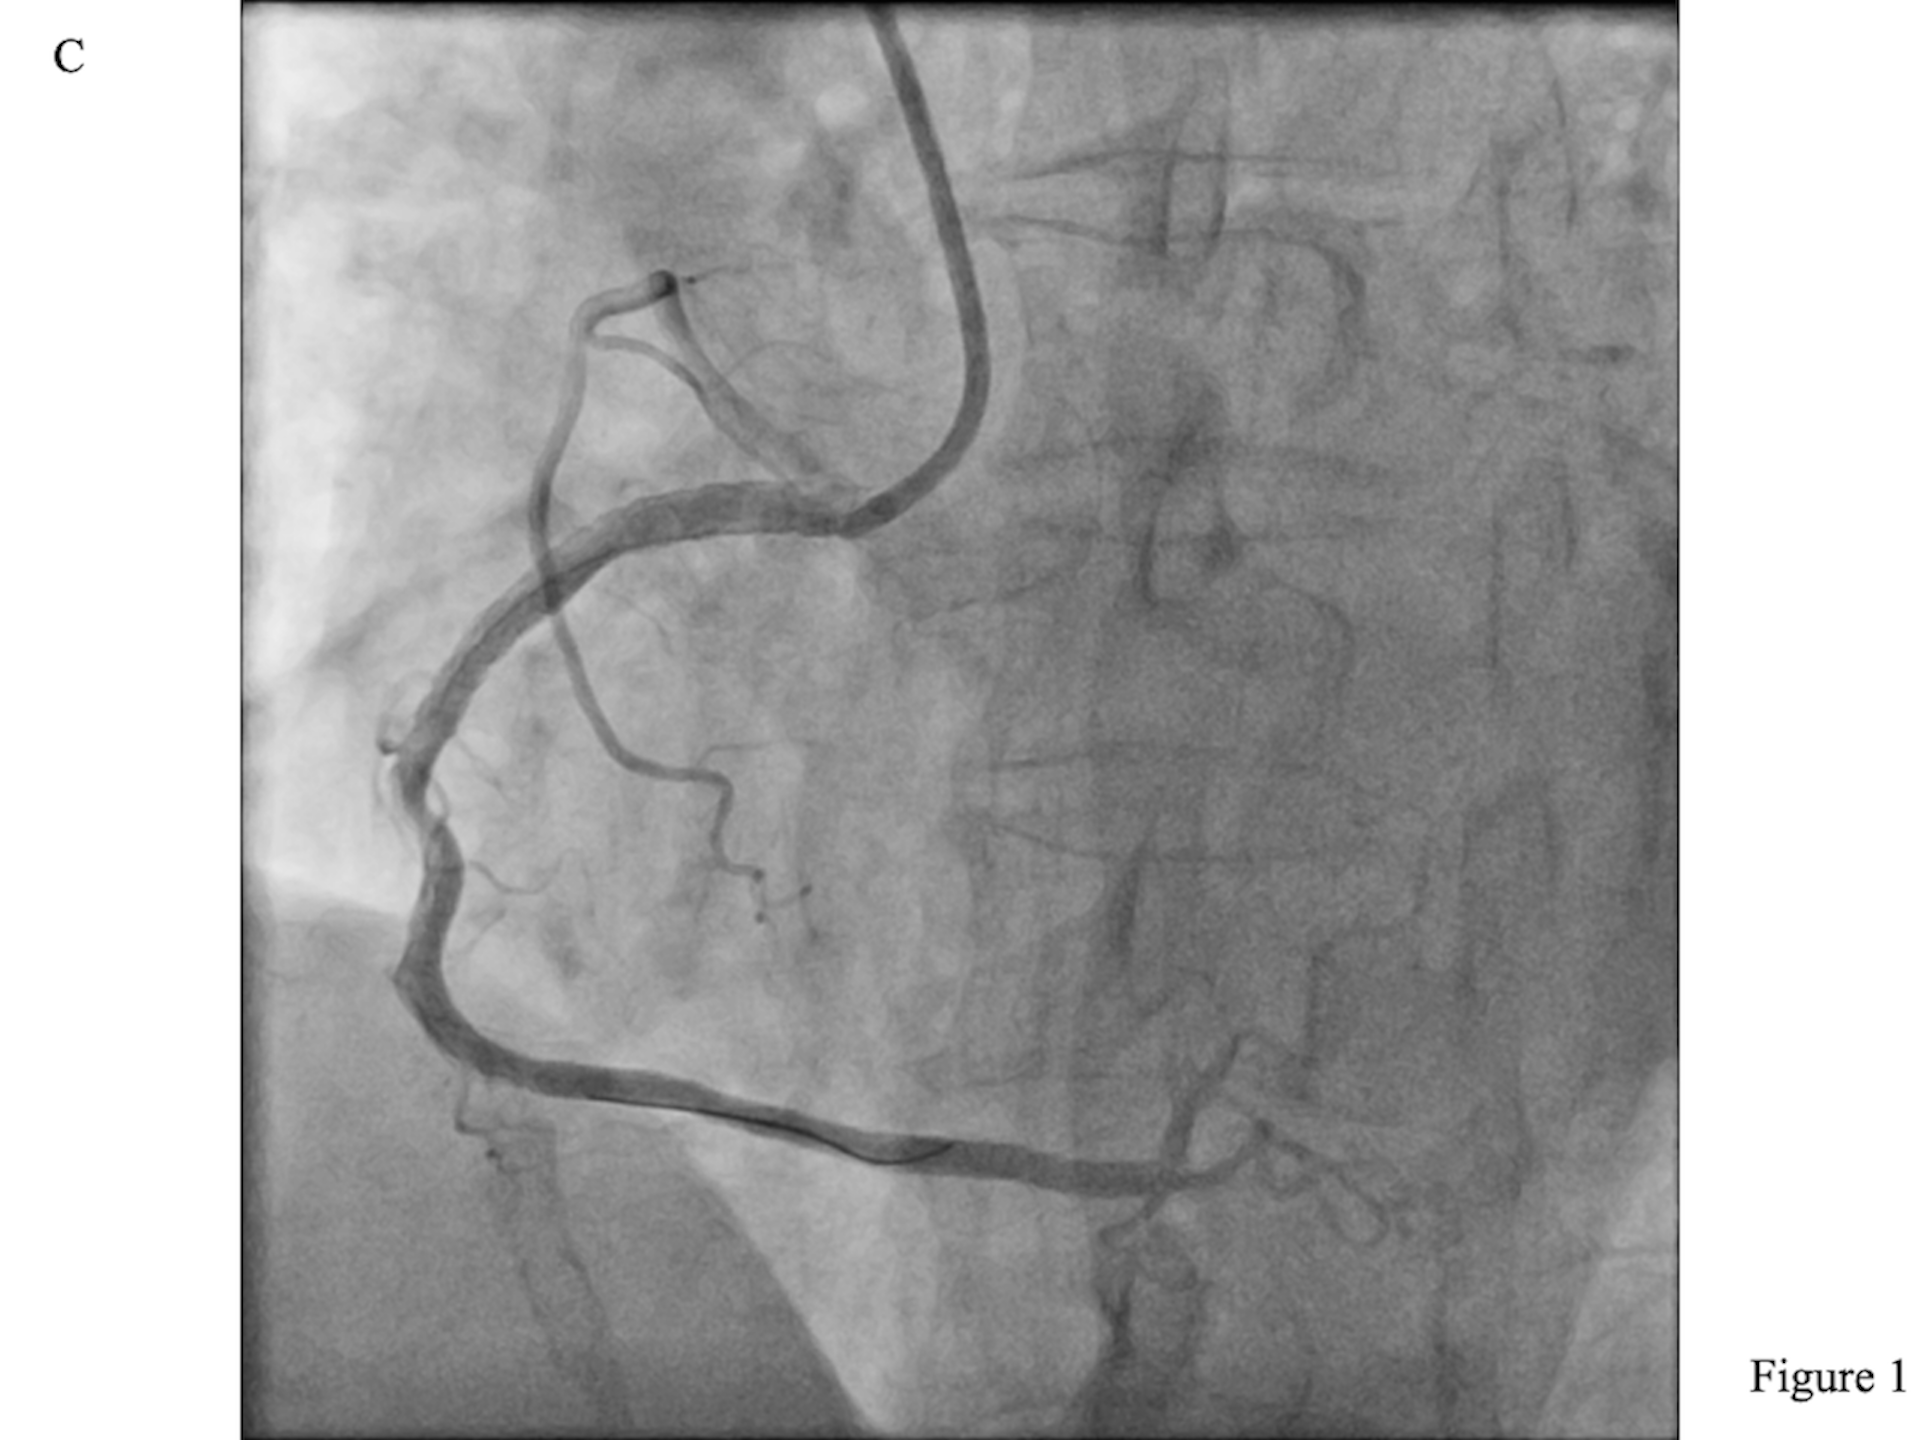

The initial rewiring entered a protruding side strut. A Sasuke dual-lumen catheter (DLC; Asahi Intecc) was inserted along the side-strut wire. The central stent lumen was then wired with another workhorse guidewire (Figure 1A, Video 1), as confirmed by intravascular ultrasound (Figure 1B, Videos 2 and 3). After post-dilatation with a 4.0-mm non-complaint balloon, the final angiographic result was good (Figure 1C, Video 4).